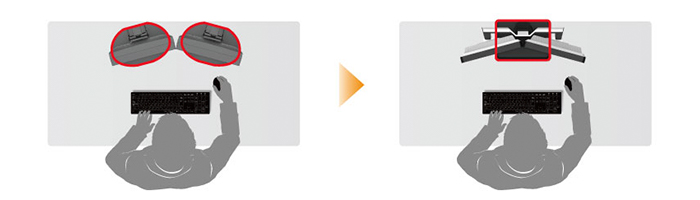

Podwójny statyw do monitorów serii i3

Optymalne wyświetlenie obrazów medycznych wymaga zastosowania dwóch monitorów. Dzięki umieszczeniu obu tych monitorów na jednym podwójnym statywie można jednocześnie regulować wysokość oraz kąty pionowy i poziomy dla obu ekranów.

Zwiększona przestrzeń robocza poprzez zmniejszenie powierzchni podstawy statywu

Powierzchnia podstawy statywu podwójnego jest o 46% mniejsza w porównaniu z powierzchnią podstaw dwóch statywów pojedynczych. Zaoszczędzone w ten sposób miejsce można wykorzystać zwiększając przestrzeń roboczą obok monitorów.